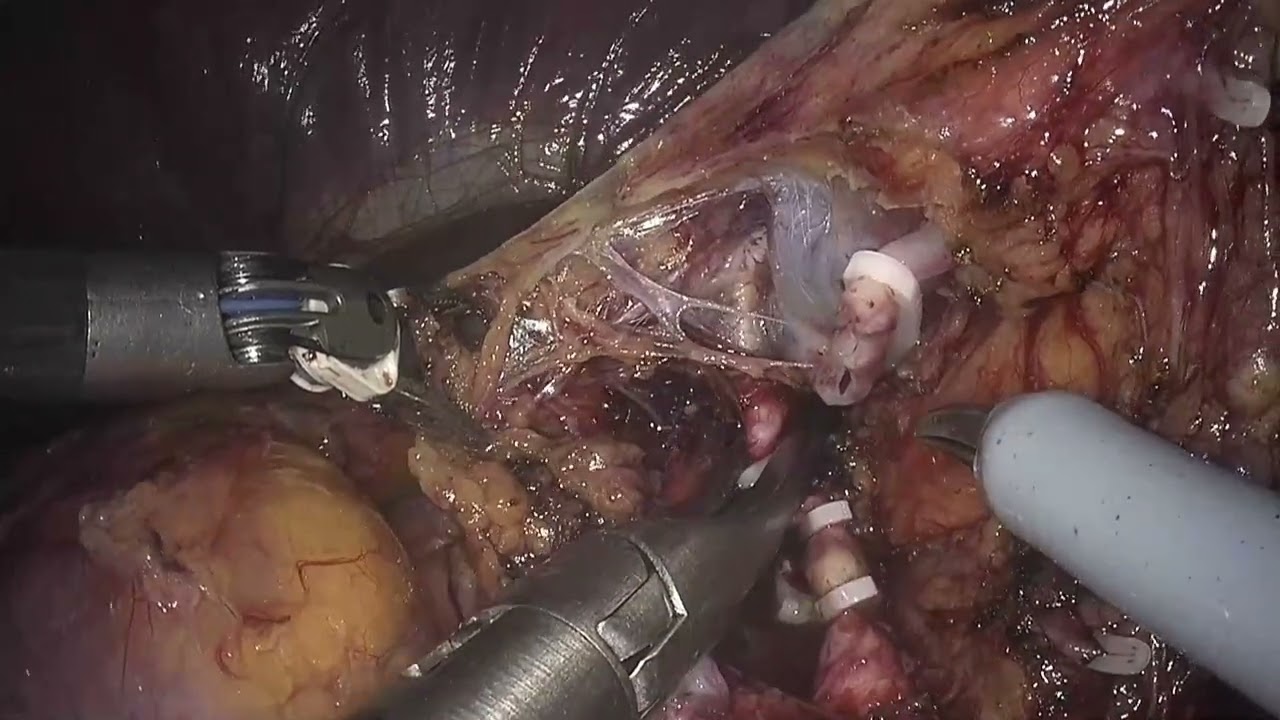

Jaipur Saturday Session 5 Hepato-Pancreato-Billiary Surgery

# 209 Robotic pancreatic tail resection Kimura procedure- Dr. George van der Schelling